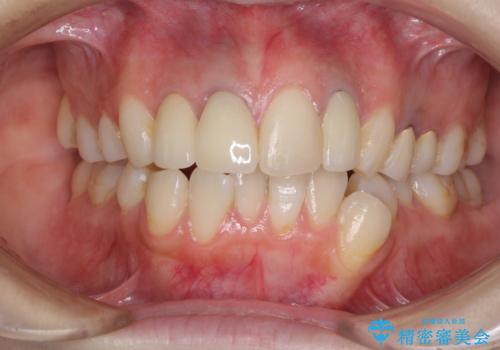

色調を統一するために、未治療の1歯もクラウンを装着するかどうか悩んでいらっしゃいましたが、結果としては治療せずに4前歯の色調を合わせることができました。

歯肉の黒ずみも多少改善させることができ、患者様には大変満足していただきました。